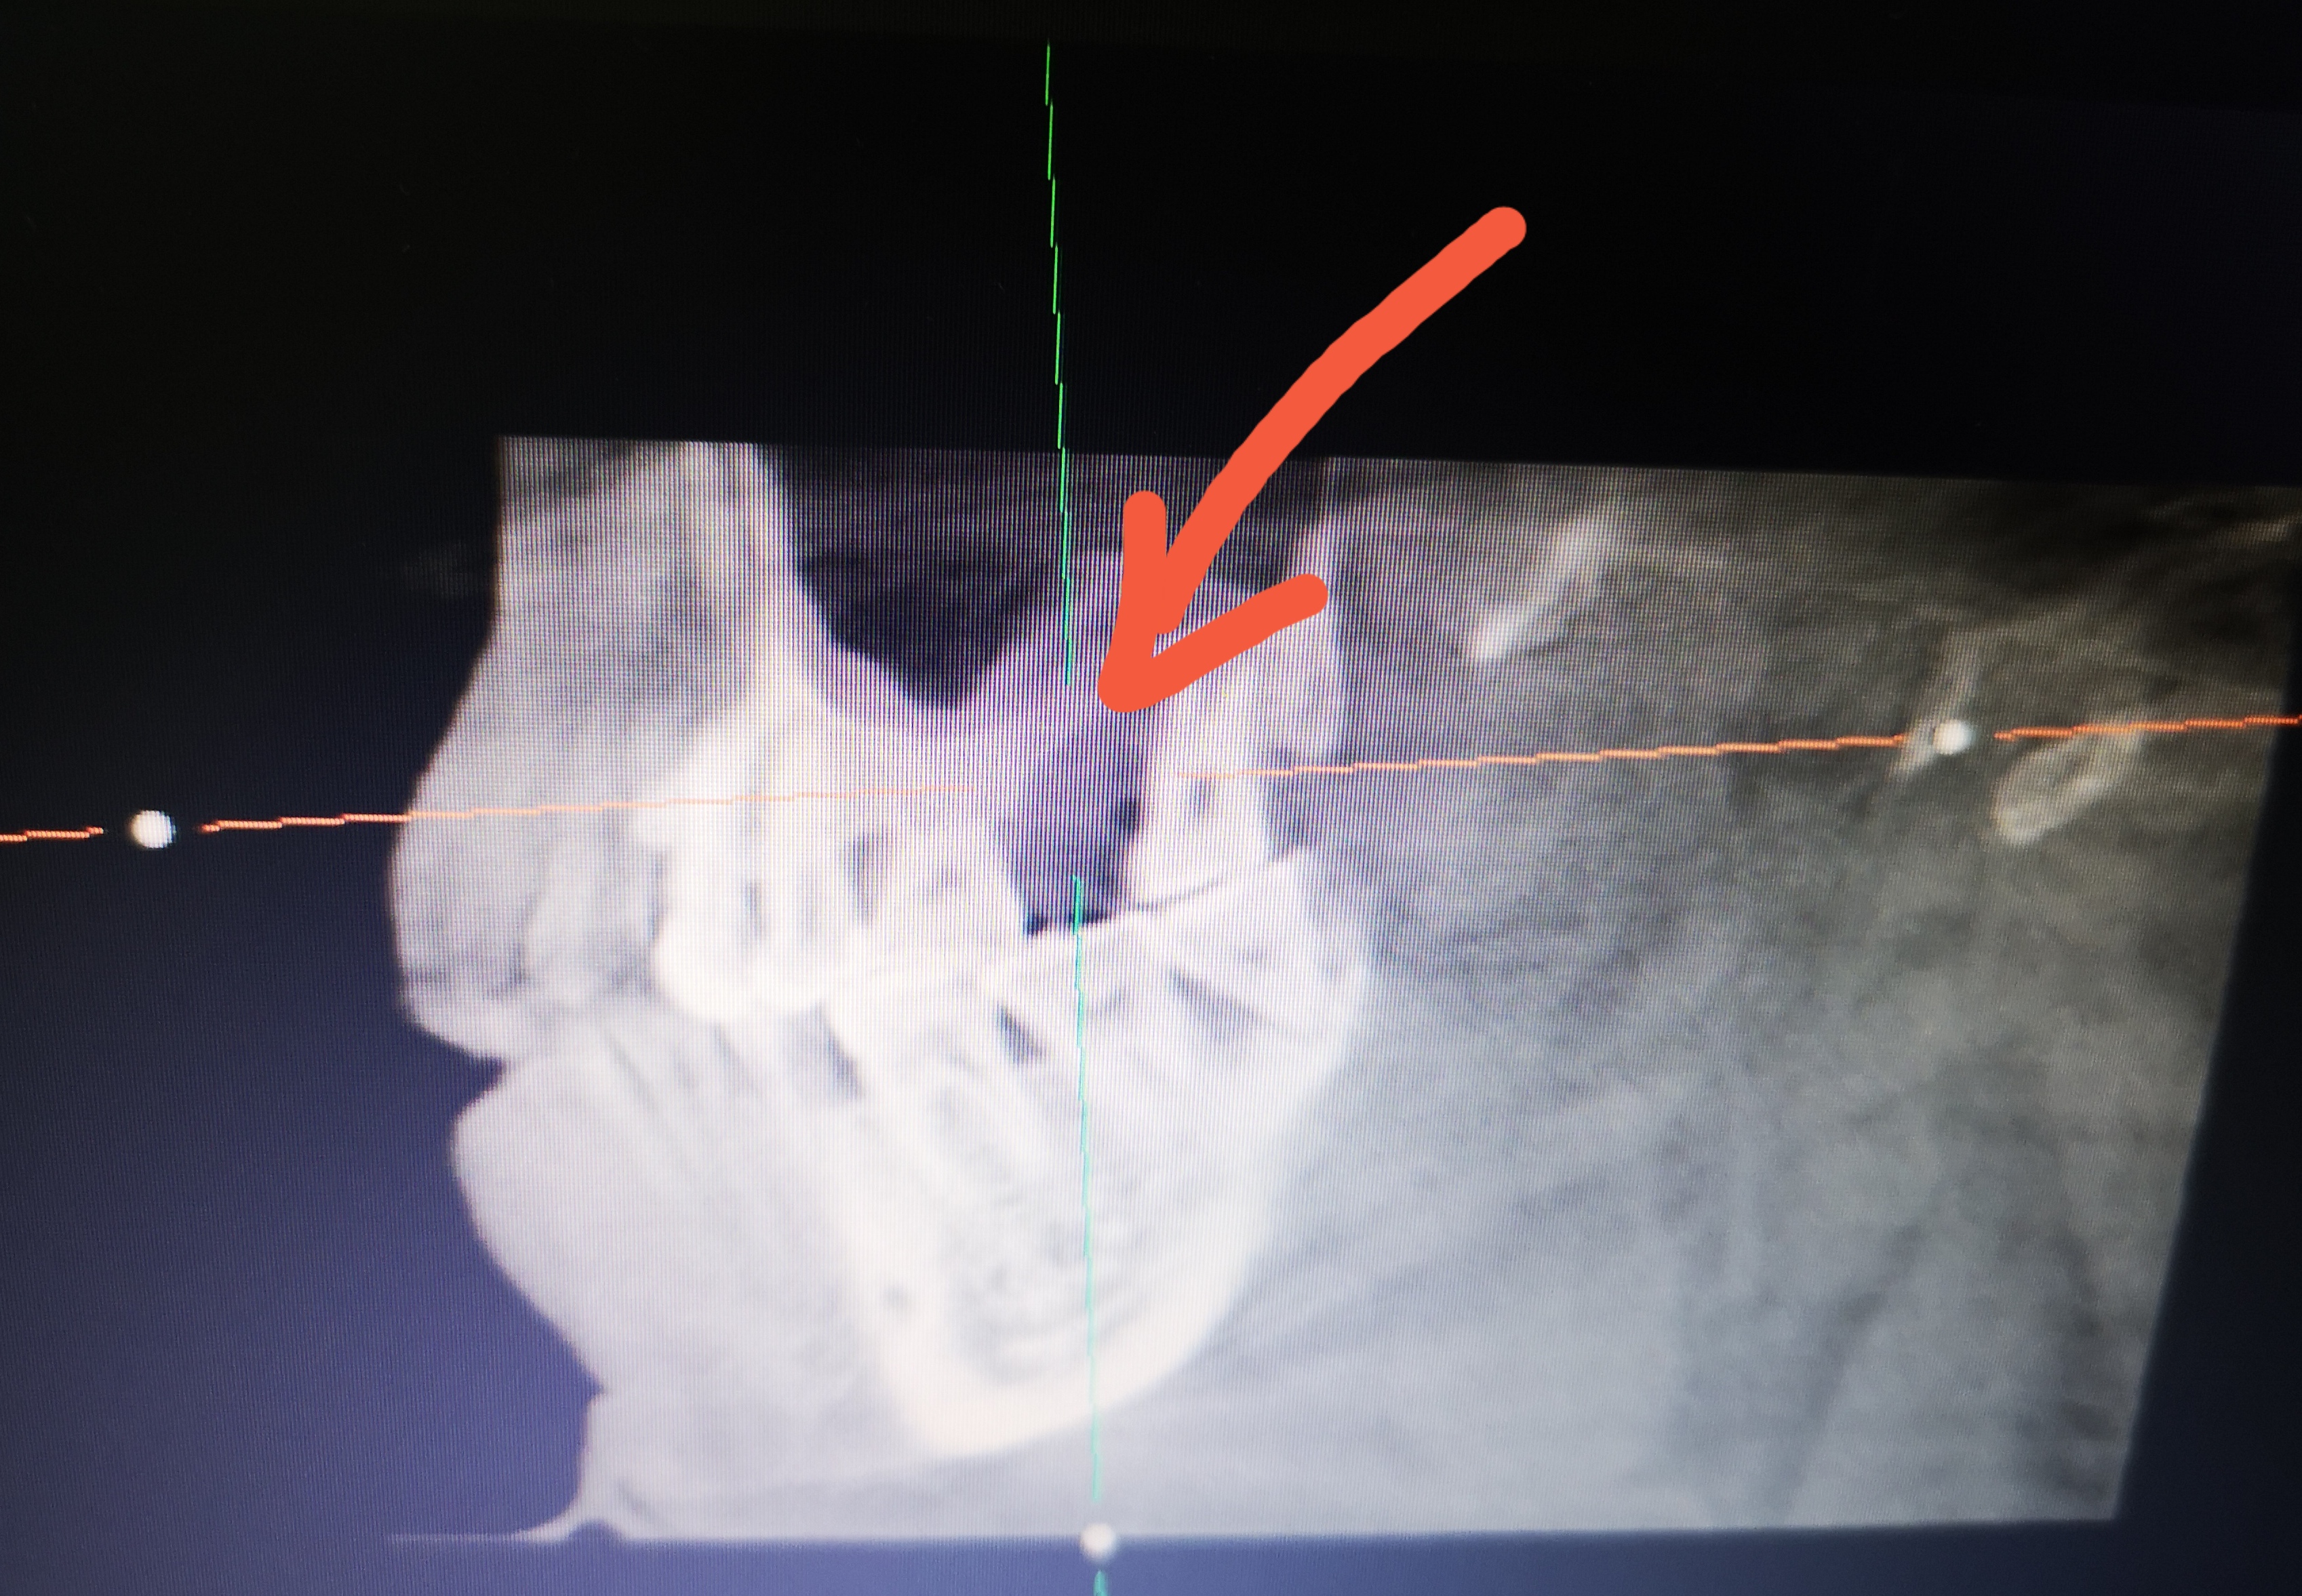

给我种植牙的是彭大夫的老师徐大夫,他先看了我的CT片子,说我的情况应该先把后面的那颗智齿拔了,再养半年后种牙才最合适。我倒是不急,啥时候种都行,反正没影响我吃饭。

种植完,又拍了一个CT片子,护士给我交待注意事项,然后就是费用的事了。彭大夫说之前是准备植骨的,但是根据实际情况,不用也可以,就用了两个可即邦(胶原蛋白)一个200.加上智齿拔除400块,额外又再多掏800块。关系到钱包的问题,该讨价还价还是不能客气的。然后给了个85折,680.省点是点。加上上次的预付款,ITI材质的进口牙,一共12880块,比在公立医院应该便宜多了。上次进行牙周治疗的时候顺便问了一下,说是一颗牙15000起步,那可能就是普通材质的牙,而ITI算是最好的材质了,对比下来,性价比还是比较高吧。